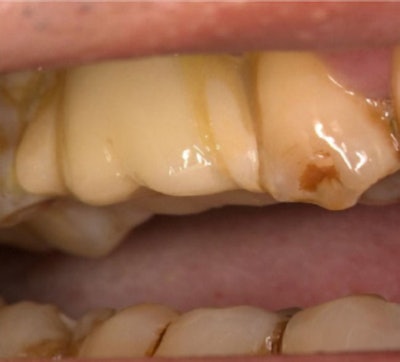

Figure 1: Dental implant proximal and distal mesial surfaces bonded to neighboring teeth with resin.Images and captions courtesy of Cheng et al. Licensed under CC BY 4.0 International.CC BY-NC-ND 4.0.